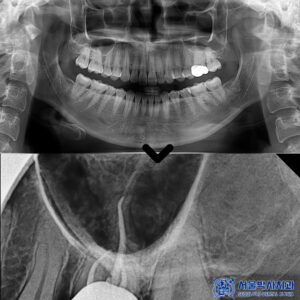

산성역치과 자연치아 살리고 싶어요. MTA 신경치료, 앞니 크라운과 레진 치료 사례

산성역치과 자연치아 살리고 싶어요. MTA 신경치료, 앞니 크라운과 레진 치료 사례 자연치아를 보존하는 것은 치아 건강을 유지하는 데 매우 중요한 요소입니다. 치아는 한 번 손상되면 원래 상태로 되돌리기…